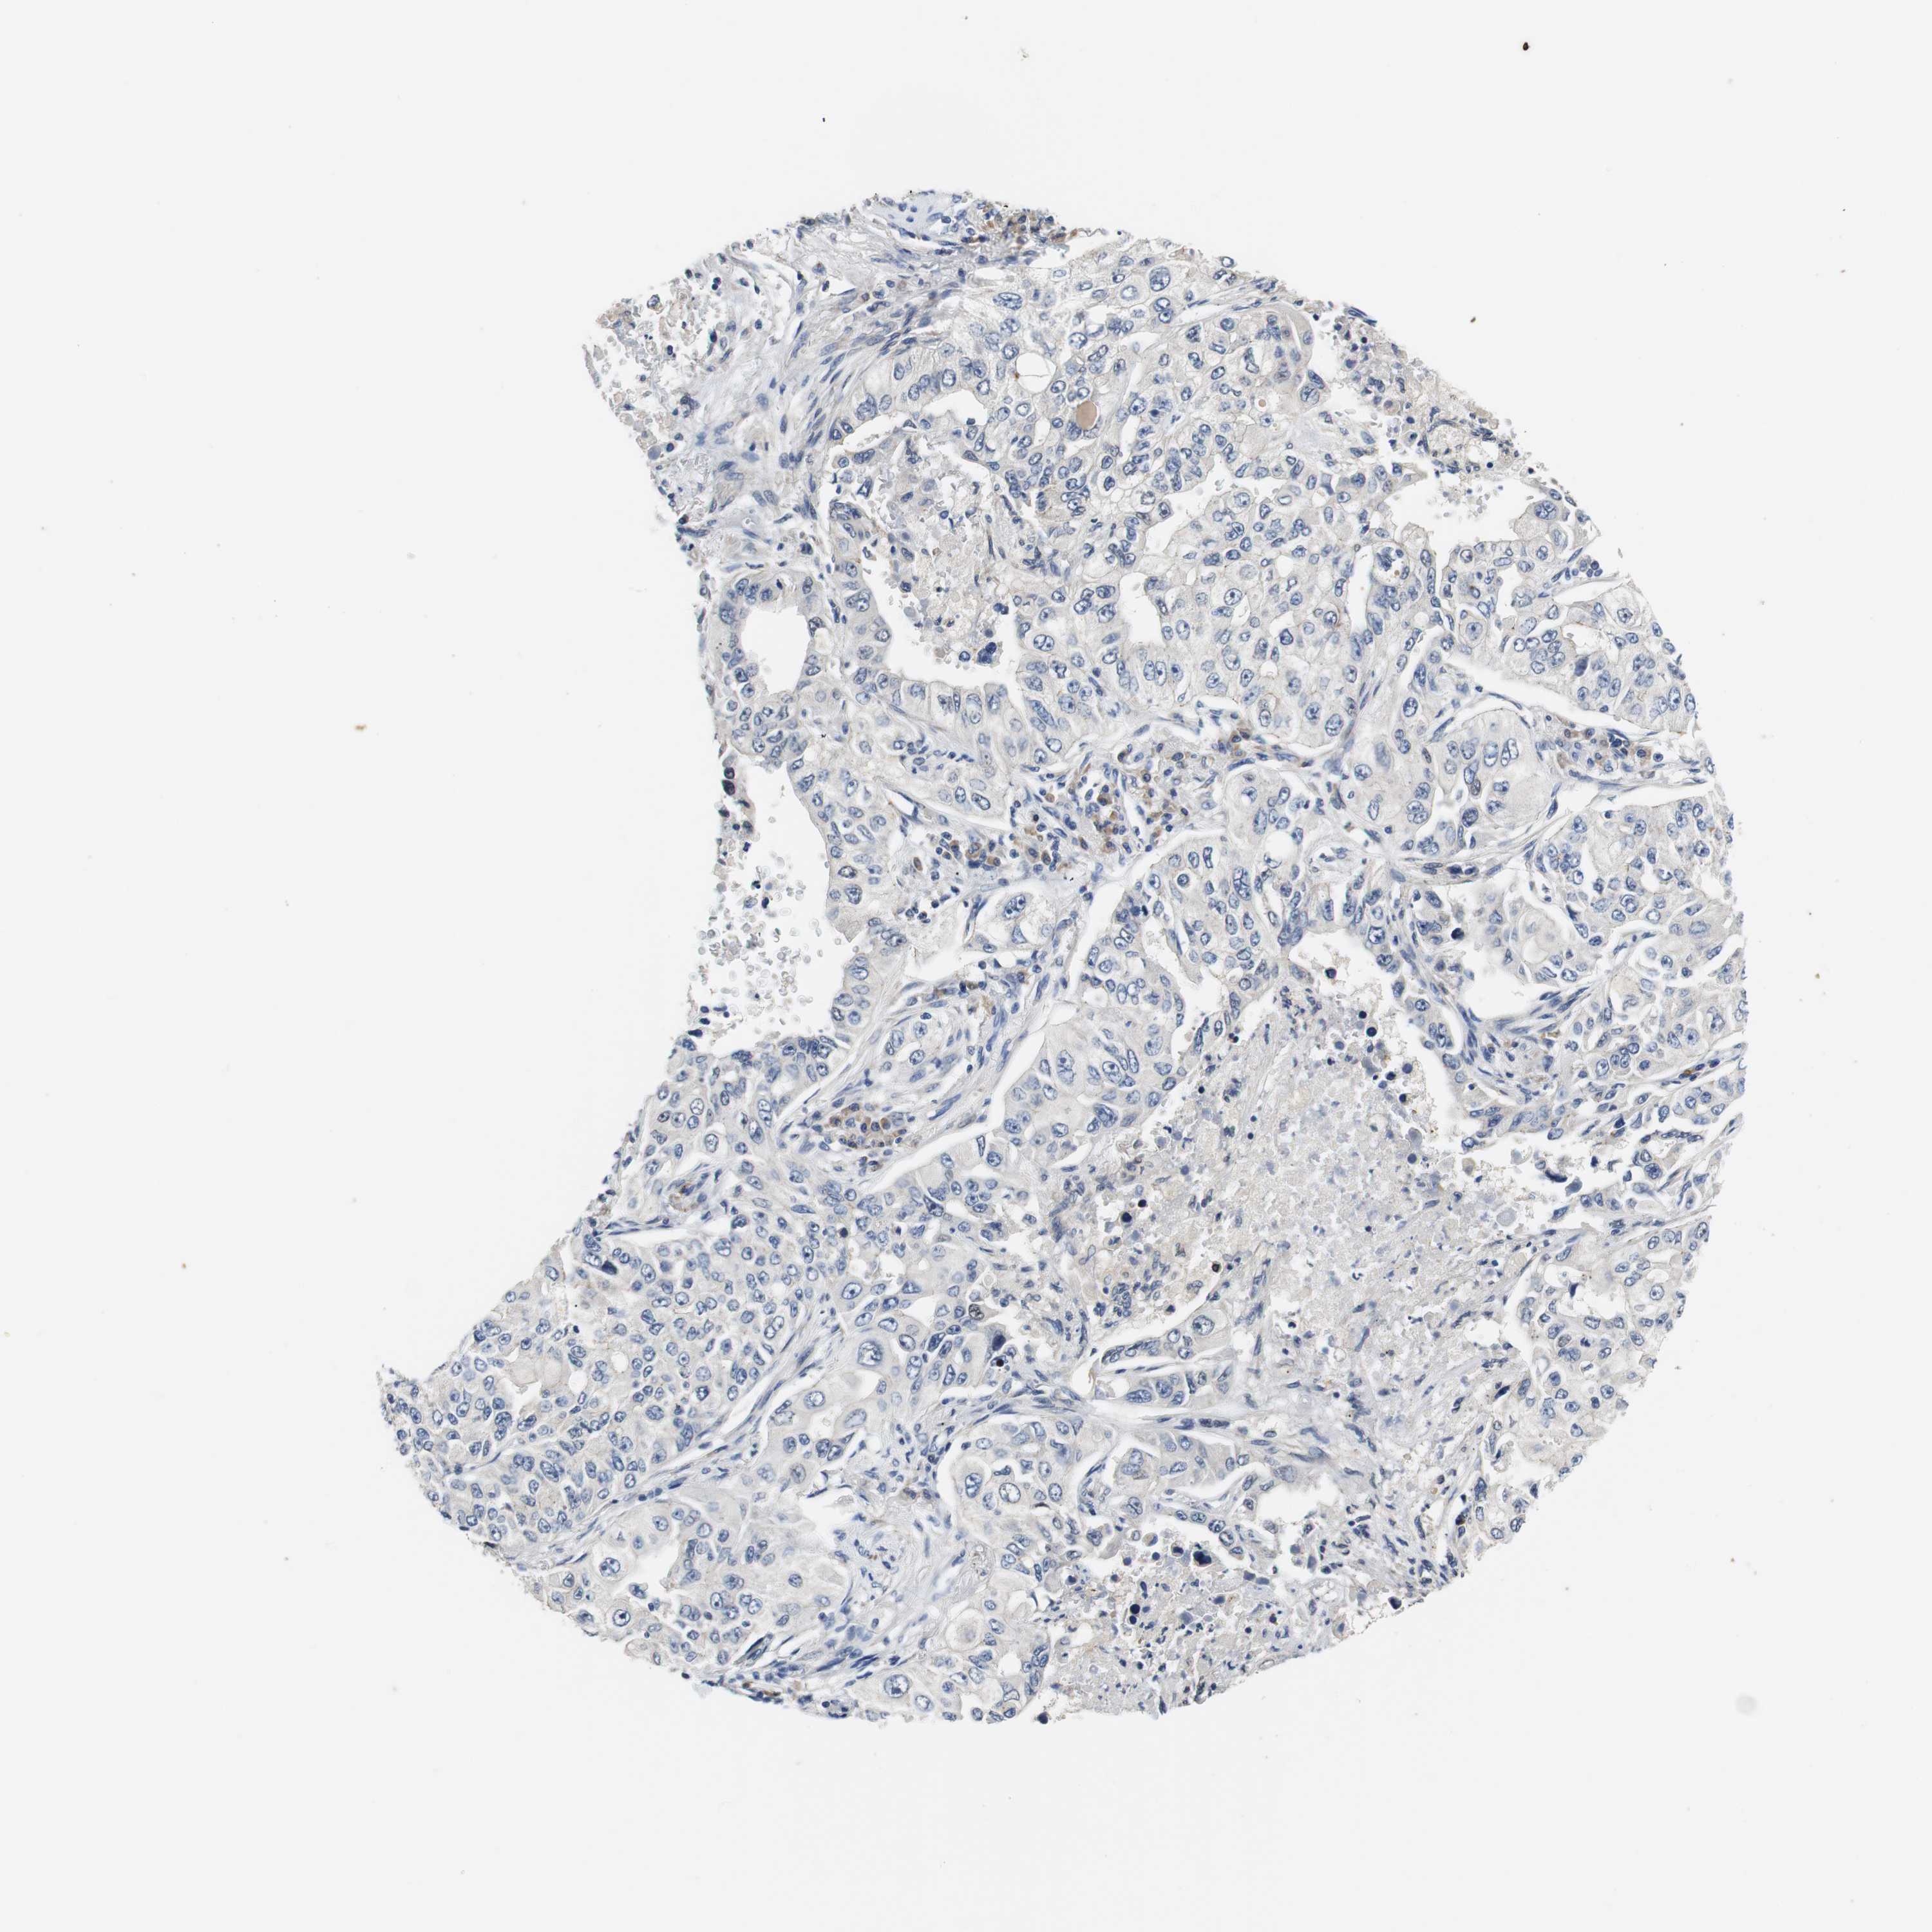

LUNG SQUAMOUS CELL CARCINOMA (TCGA) - Interactive survival scatter ploti

The Survival Scatter plot shows the clinical status (i.e. dead or alive) for all individuals in the patient cohort, based on the same data that underlies the corresponding Kaplan-Meier plots. Patients that are alive at last time for follow-up are shown in blue and patients who have died during the study are shown in red.

The x-axis shows the expression levels (FPKM) of the investigated gene in the tumor tissue at the time of diagnosis. The y-axis shows the follow-up time after diagnosis (years). Both axes are complimented with kernel density curves demonstrating the data density over the axes. The top density plot shows the expression levels (FPKM) distribution among dead (red) and alive patients (blue). The right density plot shows the data density of the survived years of dead patients with high and low expression levels respectively, stratified using the cutoff indicated by the vertical dashed line through the Survival Scatter plot. This cutoff is automatically defined based on the FPKM cutoff that minimizes the p-score. The cutoff can be changed by dragging the vertical line or by entering a cutoff value in the square labeled "Current cut-off".

Under the Survival Scatter plot the p-score landscape (black curve; left axis) is shown together with dead median separation (red curve; right axis). Dead median separation is the difference in median mRNA expression between patients who have died with high and low expression, respectively. It is calculated as follows: median FPKM expression of dead patients with high expression - median FPKM expression of dead patients with low expression. This is intended to aid the user in visually exploring custom cutoffs and the associated p-scores and dead median separation.

Individual patient data is displayed and can be filtered by clicking on one or more of the category buttons on the top of the page. Categories describing expression level and patient information include: high, low, alive, dead, female, male and tumor stages. The scale of the x-axis can be toggled between linear and log-scale by clicking on the "x log" button. Mouse-over function shows TCGA ID, patient information and mRNA expression (FPKM) for each patient.

& Survival analysisi

Kaplan-Meier plots summarize results from analysis of correlation between mRNA expression level and patient survival. Patients were divided based on level of expression into one of the two groups "low" (under cut off) or "high" (over cut off). X-axis shows time for survival (years) and y-axis shows the probability of survival, where 1.0 corresponds to 100 percent.

PCK1 is not prognostic in Lung Squamous Cell Carcinoma (TCGA)